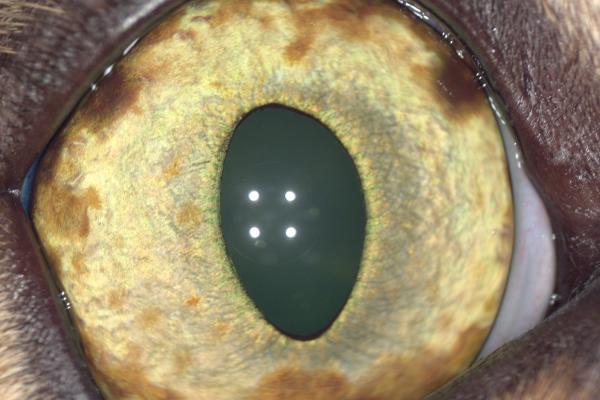

Tuto část těla postihují samozřejmě jak nezhoubné, tak často i velmi zhoubné novotvary, se špatnou prognózou.

Mezi nejčastější nálezy patří:

- primární a metastatické nádory mozku a mozkových plen,

- nádory slinných žláz,

- nádory lymfatického systému hlavy a krku,

- nádory kostí lebky a čelistí,

- nádory dutin nosních.